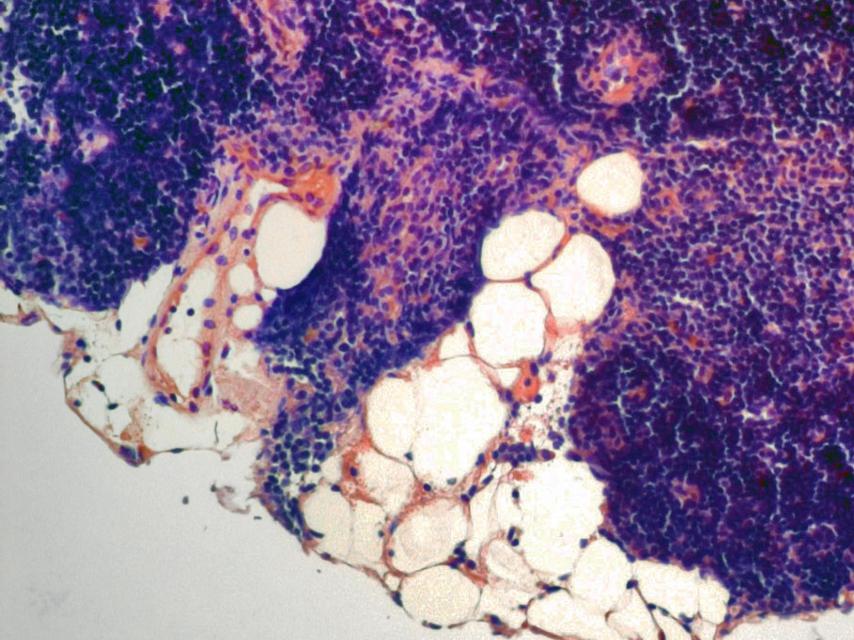

Tejido del timo degradado por el envejecimiento.

Tejido del timo degradado por el envejecimiento. Yale University